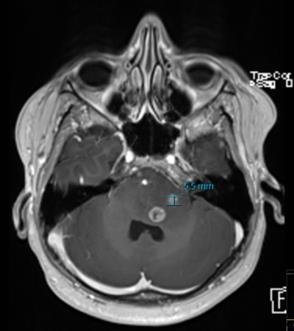

1. Til venstre: peroperativt bilde av malign og ekspansiv tumor med rik neovaskularisering. Til høyre: utdrag av MR (T1-serie med kontrast), som viser omfanget av tumor i hjernen. Kontrastladende del av tumor (CE) har vært det etablerte målet for reseksjon, men er nylig blitt erstattet med et mål om supramaksimal reseksjon som også omfatter ikke-kontrastladende tumor (nCE). Området for motorisk kontroll av høyre hånd er også markert (M).

FIGUR 3. A) Preoperativt aksialt CT-bilde av tumor med blødning. B) Preoperativt aksialt MR-bilde (T1 med kontrast) som viser høygradig tumor (oransje sirkel) og blødning (rød sirkel) med nervefiberbaner fremstilt i relasjon til tumor; kortikospinale baner i blå og fasciculus arcuatus i grønn. C) Tredimensjonal fremstilling av tumor i relasjon til nerverfiberbaner (kortikospinale baner i blå og fasciculus arcuatus i grønn). D) Preoperativt koronalt MR­bilde (T1 med kontrast) som viser høygradig tumor (oransje sirkel) og blødning (rød sirkel) med nervefiberbaner fremstilt i relasjon til tumor; kortikospinale baner i blå og fasciculus arcuatus i grønn. E) Tett samarbeid mellom nevropsykolog (til venstre), kirurg (til høyre) og pasient (i midten) under våken testfase for å ivareta språkfunksjon under reseksjon av tumor. Pasienten har samtykket til at bilde publiseres.